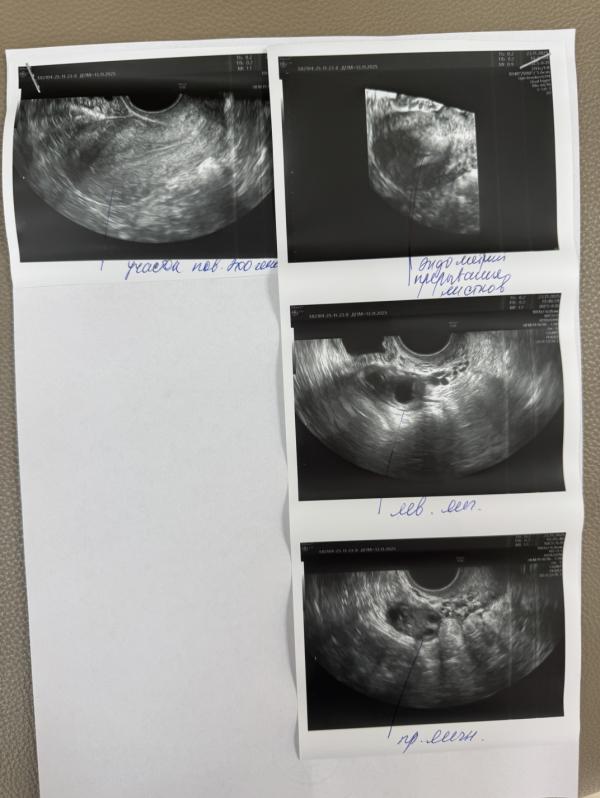

Сказали подозрение на спайки в матке. Кто нибудь беременел со спайками

у меня спайки. Только у меня матка двурогая, в правом роге есть спайки, а в левом нет. Врач сказала, что беременность может наступить в левом роге.

Она сказала, что если год не наступает беременность, то рассекать спайки, а так лишний раз проводить манипуляции в матке не стоит